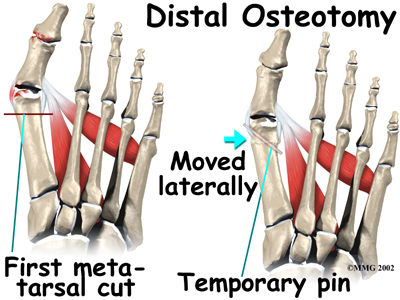

When a surgeon cuts and repositions a bone, it is referred to as an osteotomy. There are two basic techniques used to perform an osteotomy to realign the first metatarsal.

Distal Osteotomy

In some cases, the far end of the bone is cut and moved laterally (called a distal osteotomy). This effectively reduces the angle between the first and second metatarsal bones. This type of procedure usually requires one or two small incisions in the foot. Once the surgeon is satisfied with the position of the bones, the osteotomy is held in the desired position with one, or several, metal pins. Once the bone heals, the pins are removed. Removing of the pins usually occurs between three and six weeks following surgery.